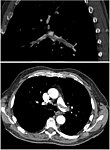

Ventilation-perfusion scintigraphy

(A) After inhalation of 20 mCi of Xenon-133 gas, scintigraphic images were obtained in the posterior projection, showing uniform ventilation to lungs.

(B) After intravenous injection of 4 mCi of Technetium-99m-labeled albumin, scintigraphic images shown here in the posterior projection. This and other views showed decreased activity in multiple regions.

A ventilation/perfusion scan (or V/Q scan or lung scintigraphy) shows that some areas of the lung are being ventilated but not perfused with blood (due to obstruction by a clot).[17] This type of examination is as accurate as multislice CT, but is less used, due to the greater availability of CT technology. It is particularly useful in people who have an allergy to iodinated contrast, impaired kidney function, or are pregnant (due to its lower radiation exposure as compared to CT).[56][57][58] The test can be performed with planar two-dimensional imaging, or single photon emission tomography (SPECT) which enables three-dimensional imaging.[49] Hybrid devices combining SPECT and CT (SPECT/CT) further enable anatomic characterization of any abnormality.